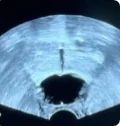

Procedural scan showing placement of the BioProtect Balloon Spacer in a salvage case. Saggital view.

Saggital Ultrasound

Image courtesy of Dr. Neil Wijetunga, Radiation Oncologist.